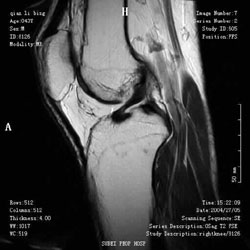

創傷後骨髓炎常見患者部位診斷依據:1.開放骨折和骨折手術固定後出現:高熱、紅腫、疼痛。2.X線片顯示:碎骨片壞死、暴露骨端壞死。

療效評價:1.治癒:全身及局部症狀消失、X線片顯示病變已修復或穩定。2.好轉:全身及局部症狀體徵好轉、X線片顯示病變未繼續發展。3.未愈:全身及局部症狀體徵未改善、X線片顯示病變繼續擴散。

創傷後骨髓炎骨質透視(1)急性期立即敞開創口引流,以免膿液迸入骨髓腔內。